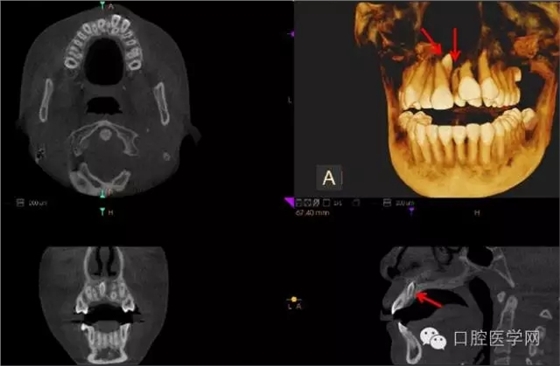

4.阻生牙

最常見(jiàn)于下頜第三磨牙

X線表現(xiàn):確定阻生牙的位置;確定阻生方向;牙根數(shù)目和形態(tài);阻生牙有無(wú)齲齒和根尖情況;與第二磨牙的關(guān)系;與下頜管的距離和磨牙后間隙的大小。